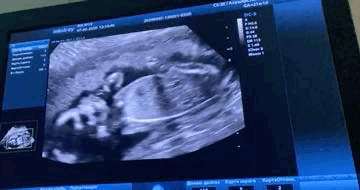

20 недель, кнопка пальчик сосет 🥰